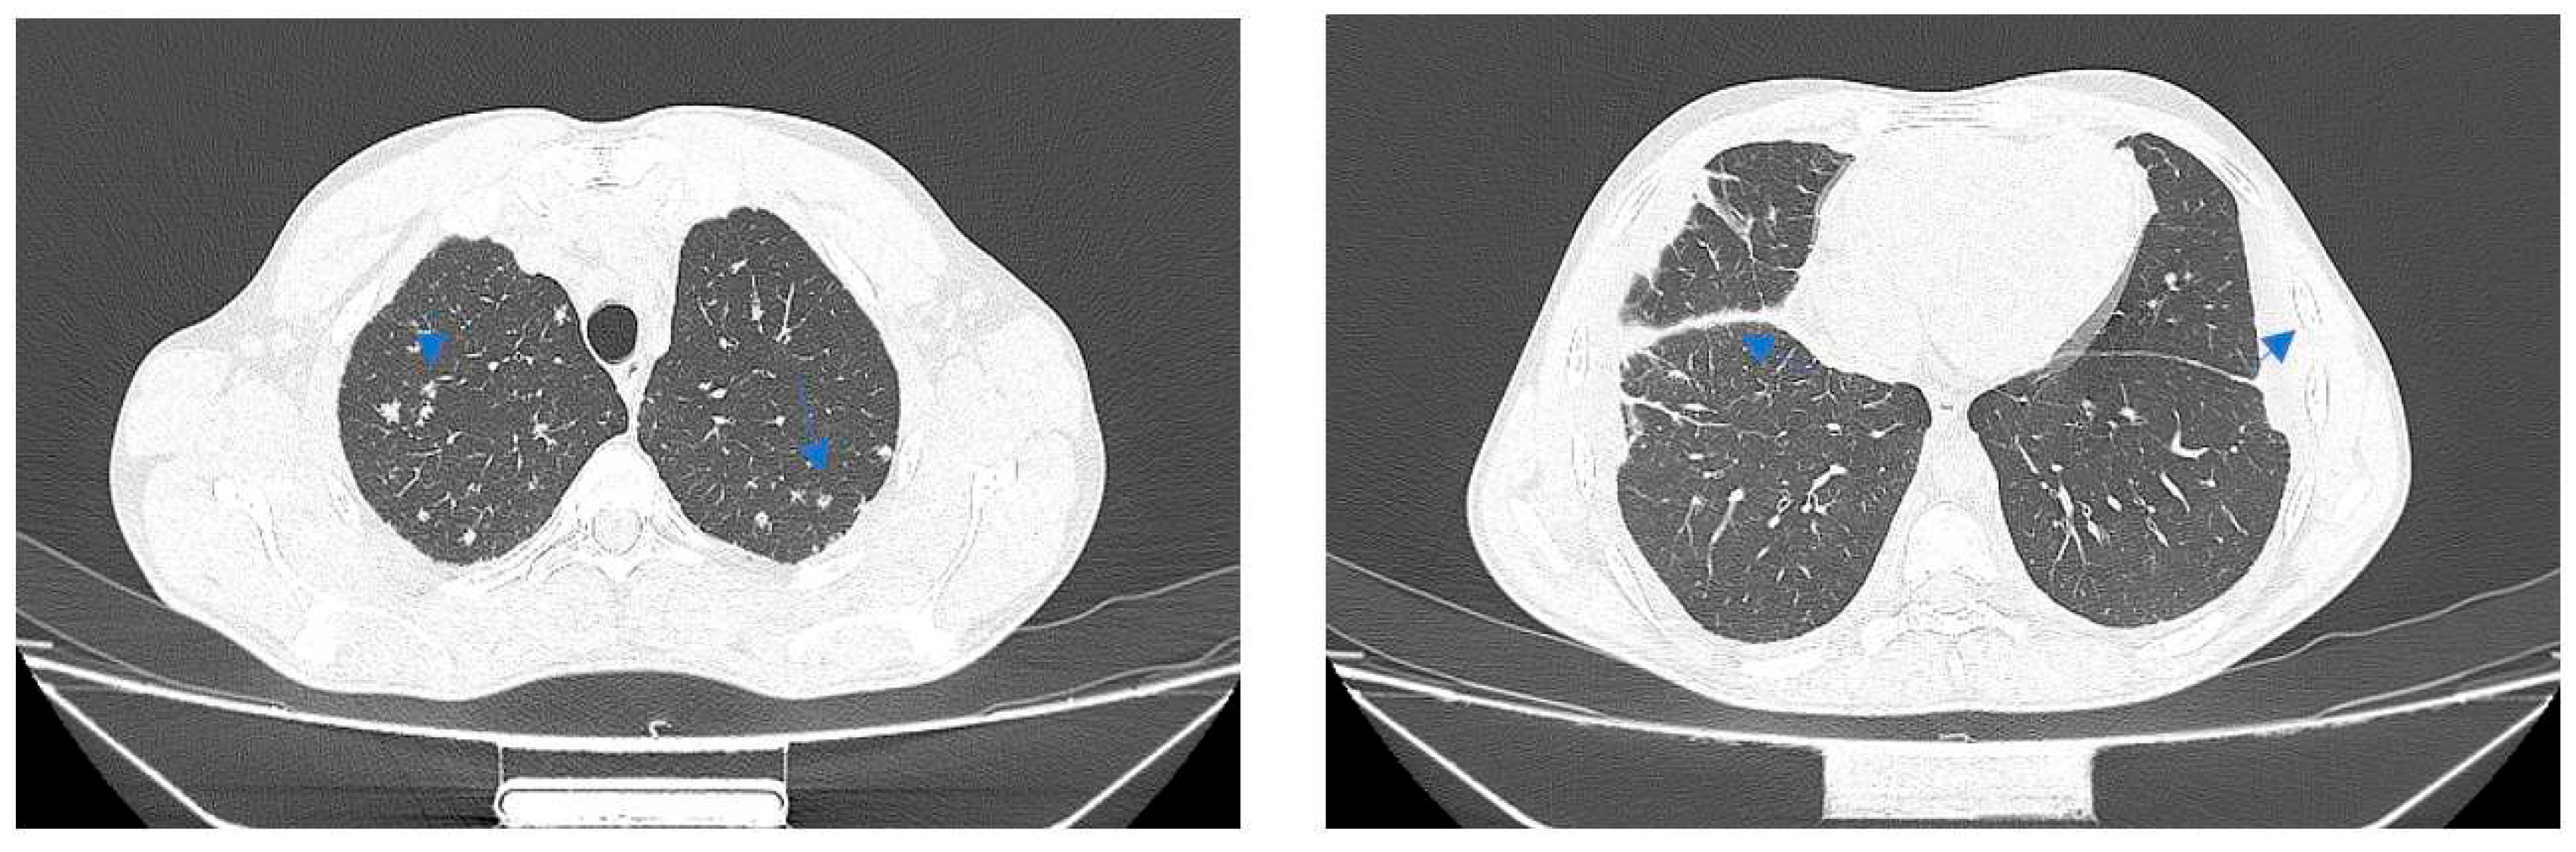

Case no 1.

Case no. 2